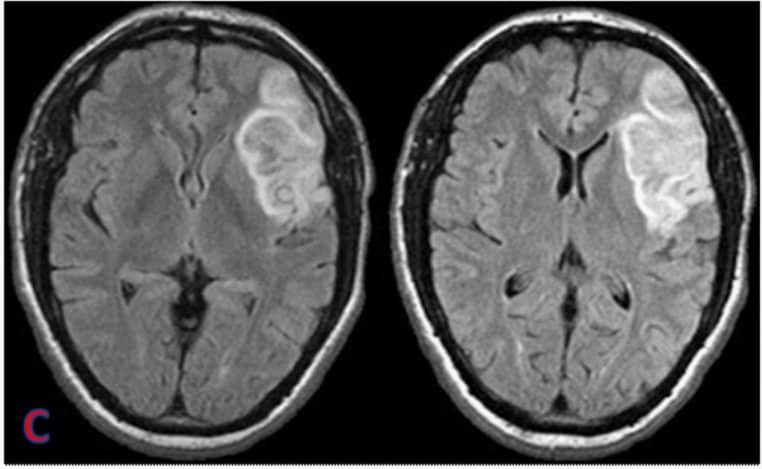

Ce que l’IRM révèle, parfois bien après

Les AVC silencieux laissent des traces typiques visibles en IRM (séquences FLAIR, DWI/ADC ou T2*) : zones d’hyperintensité ou de nécrose témoignant d’un infarctus ancien, parfois multiple. Plus ces traces s’accumulent, plus le risque de troubles cognitifs et de démence vasculaire augmente à long terme. Cela explique pourquoi la prévention vasculaire a un impact direct sur la santé du cerveau.